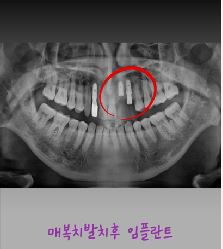

제목 매복발치후 임플란트

연수 퍼스트 치과에서는  난이도 있는 매복발치와 임플란트를~

3D CT 정밀 진단을 통해 신경과 뼈 상태를 정확히 파악하고

최소 절개로 안전하게 매복치를 발치한 후

잇몸과 뼈 상태에 맞춰 임플란트 치료를 체계적으로 진행합니다.

매복발치 후 임플란트는 난이도가 높은 치료인 만큼,

풍부한 임상 경험과 철저한 사후 관리가 중요합니다.

자연치아와 유사한 기능 회복과

오래 사용할 수 있는 안정적인 결과를 목표로 치료합니다.